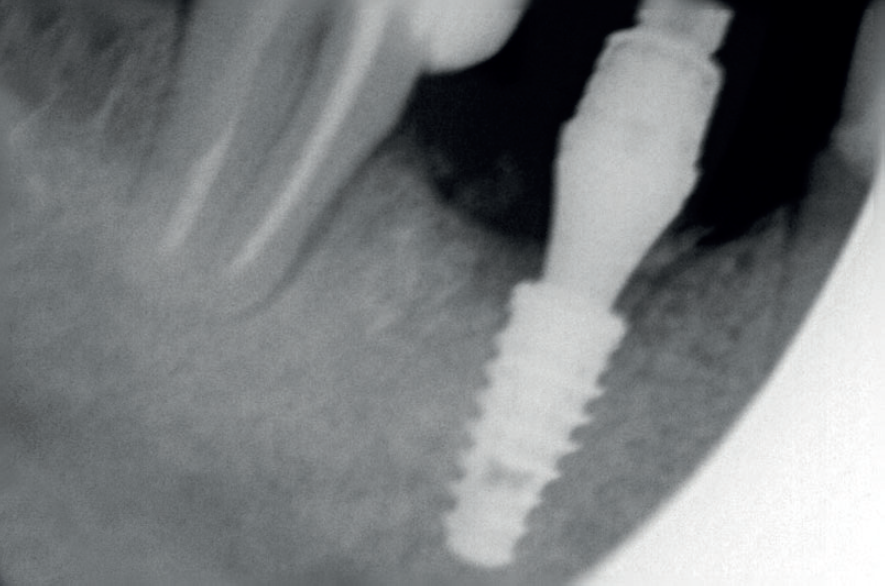

Para a regeneração óssea guiada, o substituto ósseo natural composto por hidroxiapatita bovina e colágeno do tipo I (Extra Graft XG-13) foi introduzido ao redor do implante para preenchimento do GAP (Figura 7). Depois, uma barreira regenerativa não absorvível (Cytoplast) foi recortada, adaptada e colocada, seguida por uma membrana biológica bovina (Figuras 8 e 9). O procedimento cirúrgico foi finalizado com a realização da sutura com fio de nylon 5.0. Para verificar o posicionamento do implante dentário, uma radiografia periapical foi realizada imediatamente à cirurgia (Figura 10).